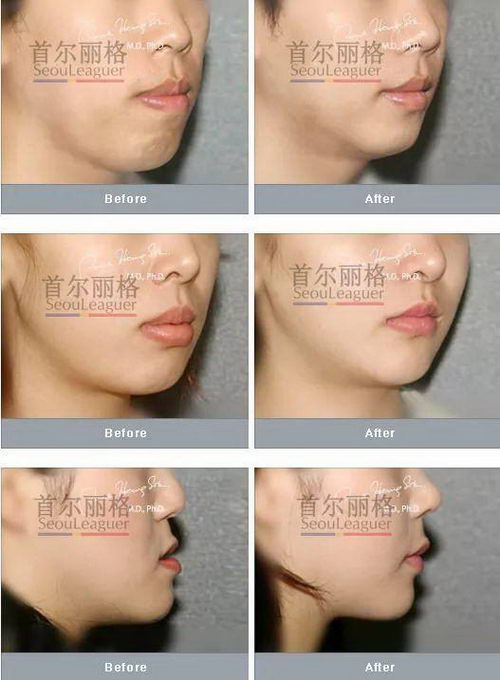

▲凸嘴手术术后2个月对比照

▲丽格双鄂凸嘴手术案例